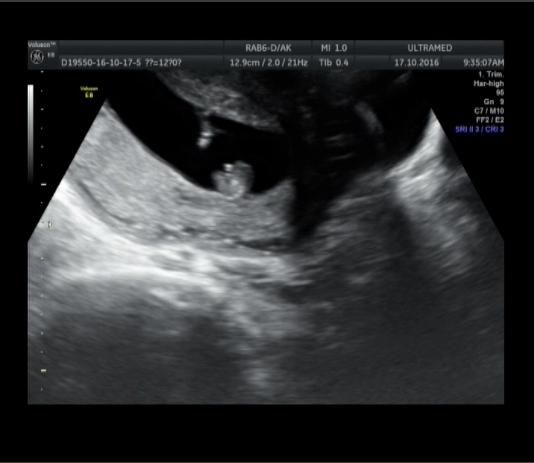

А это вид снизу: попка и ножки, а самое светлое пятно - наши органы.